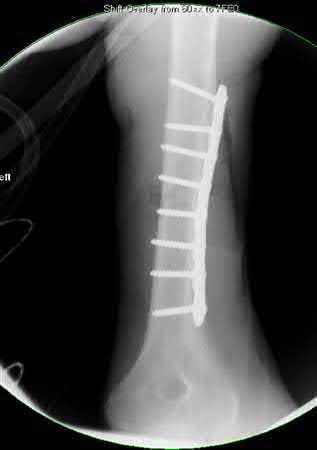

What is the most common type of malalignment after intramedullary nailing of distal 1/3 extra-articular tibia fractures using a infrapatellar approach when compared with plating?

The most common type of malalignment after intramedullary nailing of distal 1/3 extra-articular tibia fractures using an infrapatellar approach when compared with plating is valgus malalignment.

Fixation of distal one-third tibial shaft fractures can be successfully treated with either intramedullary nailing or plating. The literature describes advantages and disadvantages to both approaches, however intramedullary nailing has been shown to lead to increased rates of valgus malunion. Recent studies have shown that using a suprapatellar approach may decrease the incidence of valgus malalignement.

Vallier et al performed a randomized prospective study to compare plate and nail stabilization for distal tibia shaft fractures by assessing complications and secondary procedures. One-hundred and four patients were randomized to either reamed intramedullary nailing, or medial distal tibia plate fixation.

Primary angular malalignment was identified in 17 patients (16.3%). This included four patients treated with tibial plating (8.3%) and 13 patients treated with nails (23%, P = 0.02). Eight of these (7.7% of all patients) had malalignment between 6° and 10° of angulation. Valgus was the most common

angular deformity, accounting for 70% of angular deformity cases.